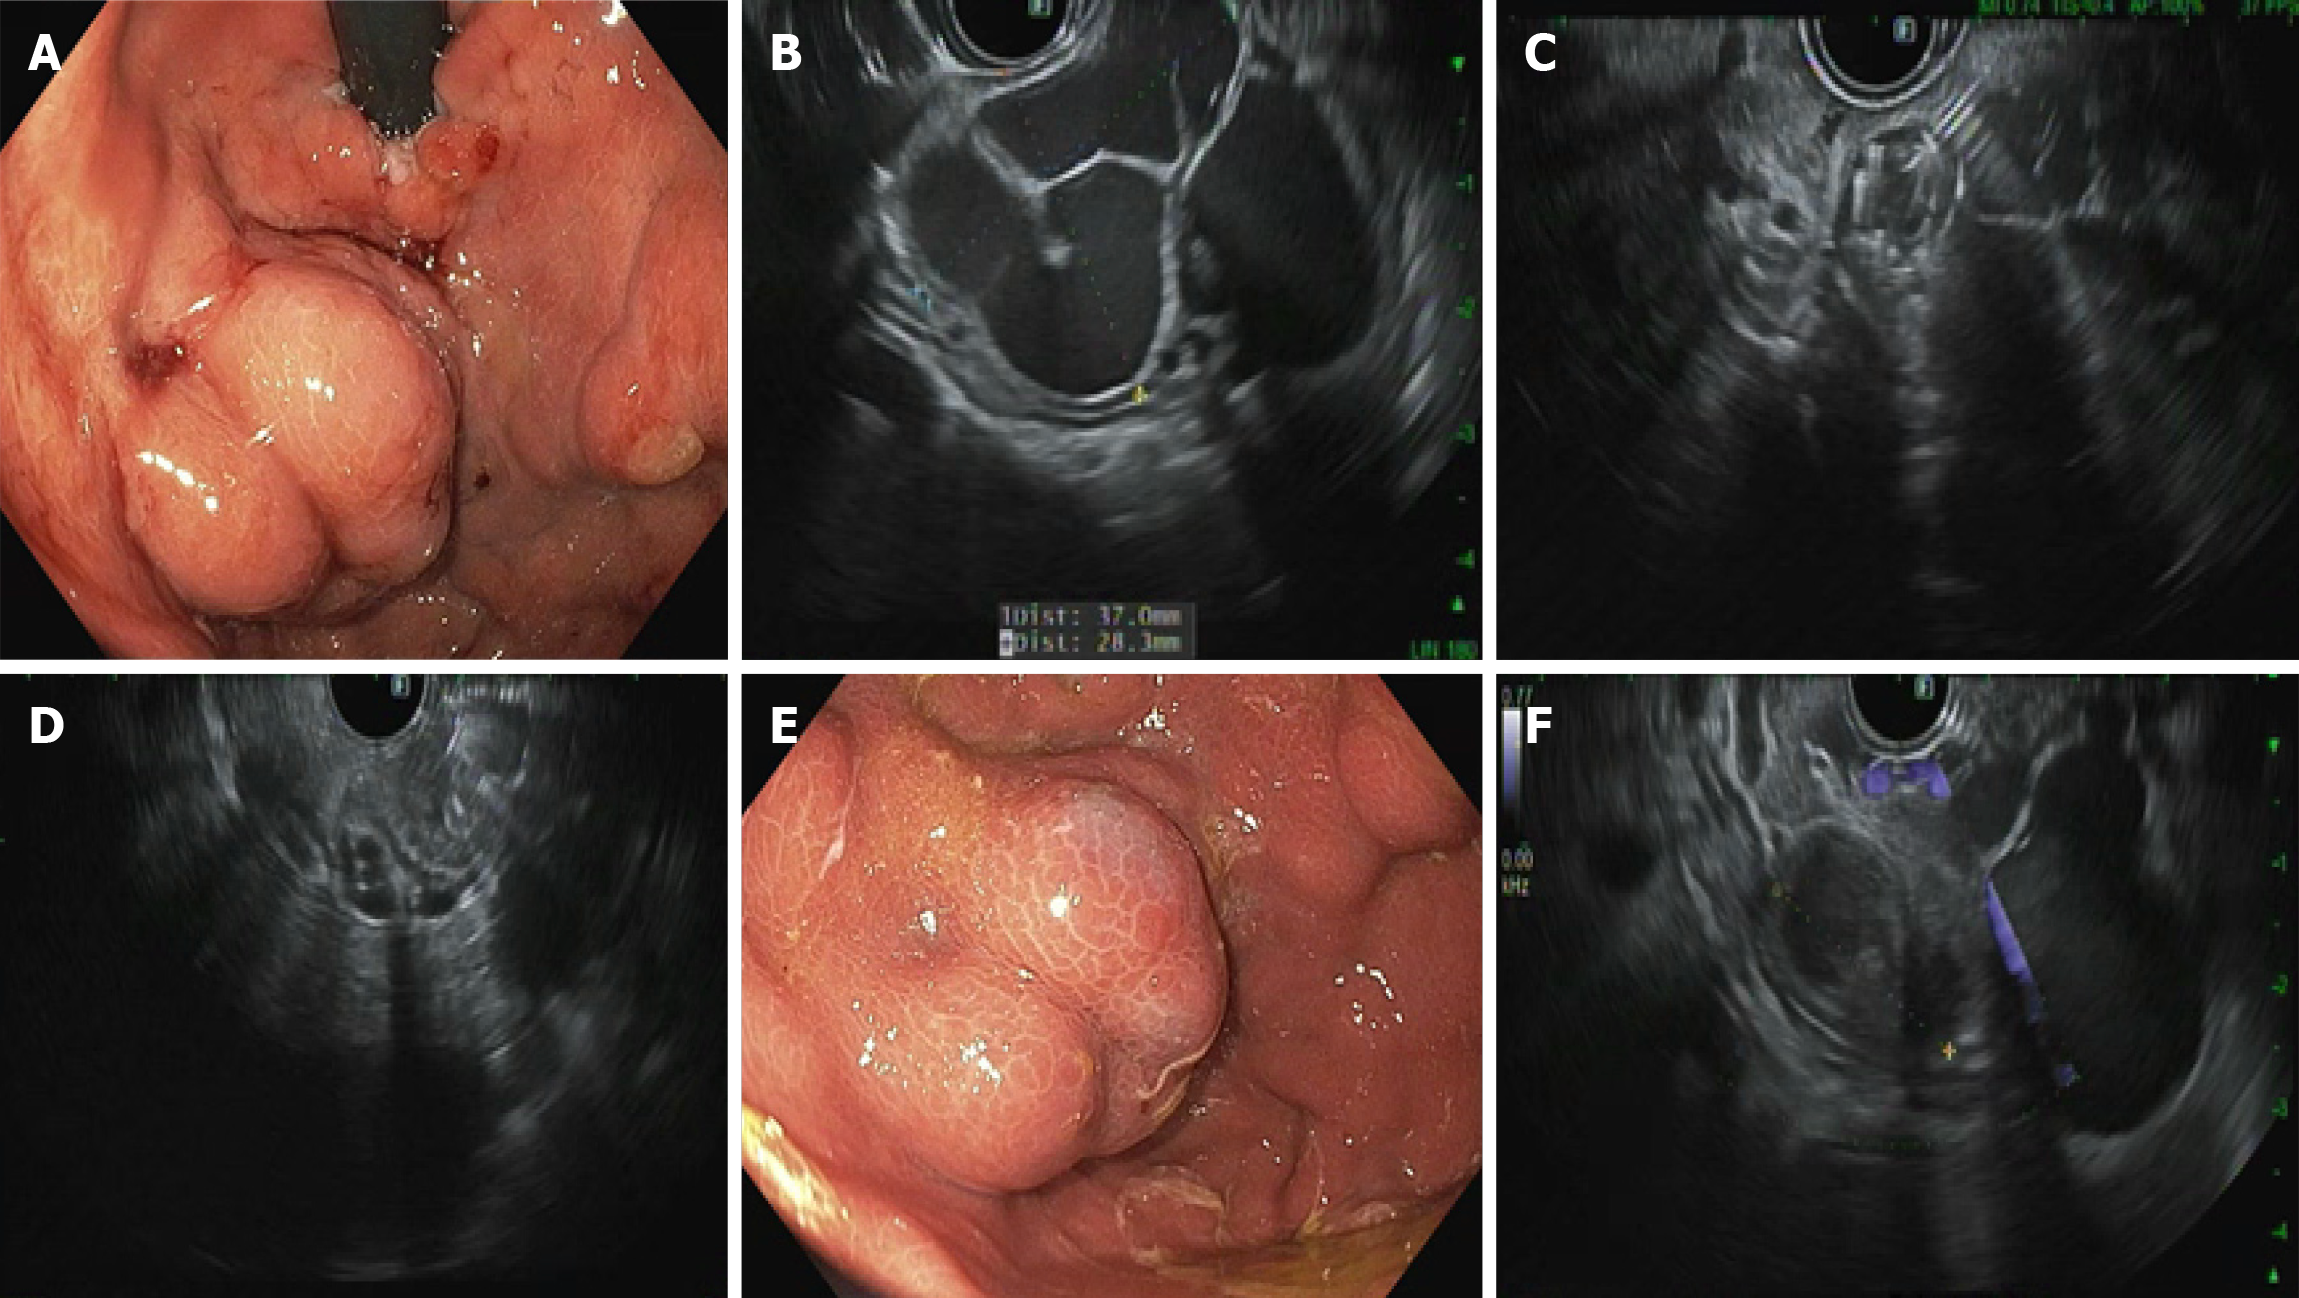

Figure 1

Figure 1 32-year-old male with history of cirrhosis secondary to alcohol use was referred for primary prophylaxis of gastric variceal bleeding. A: Upper endoscopy showed large type 1 isolated gastric variceal conglomerate; B: Endoscopic ultrasound showing a 3.7 cm variceal conglomerate; C: Trans-gastric deployment of coils through a 19-gauge needle; D: Endoscopic ultrasound showing thrombosis of targeted gastric varix; E: Follow-up endoscopy at 1 month showing smaller varices with cracked earth pattern suggesting obliteration; F: Absent flow on Doppler.